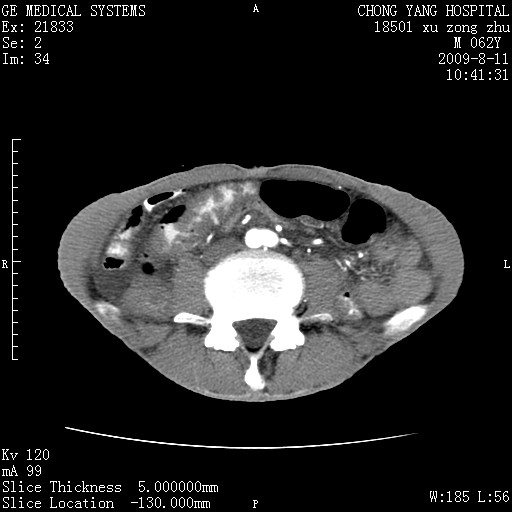

以下是引用杀毒软件在2009-8-11 16:35:00的发言:[br]肝内胆管扩张局限于左叶,胆管内有结石伴肝外胆管结石,胆管壁增厚呈弥漫性并发腹腔积液,胰腺边界模糊。[br][br]考虑---胆总管及肝内胆管结石继发胆管炎及胰腺炎,左肾下极囊肿,腹水。

以下是引用zjzjr在2009-8-11 17:35:00的发言:[br]肝内胆管扩张局限于左叶,胆管内有结石伴肝外胆管结石,胆管壁增厚呈弥漫性并发腹腔积液。[br][br]考虑---胆总管及肝内胆管结石继发胆管炎,左肾下极囊肿,腹水。